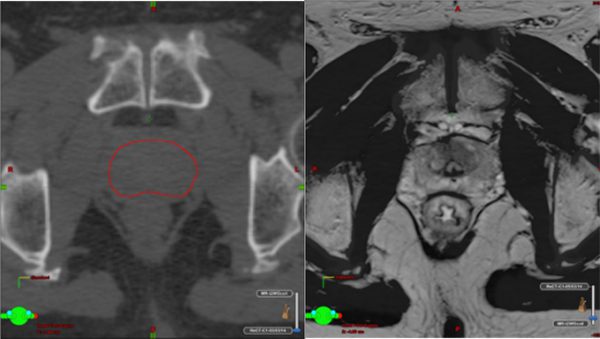

MRI-guided target definition at planning. In addition to the CT simulation scan, the patient undergoes an MRI scan of the prostate, usually on the same day. The MRI images are superimposed on the CT simulation images, allowing the radiation oncologist to define the prostate and tumour accurately. Important normal structures like the urethra (urine pipe) and penile bulb (organ associated with potency) are much more easily seen on MRI and allow the radiation oncologist to ensure that these are not overdosed.

Left – CT simulation scan of the prostate outlined with aid of MRI scan (right) which shows with much greater clarity prostate gland